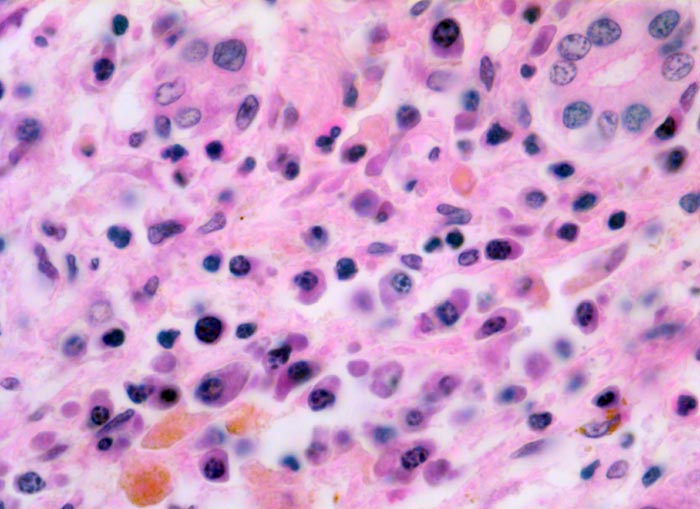

Das histologische Bild der akuten Hepatitis vom Virustyp ist gekennzeichnet durch eine lobuläre Entzündung bei fehlender portaler Fibrose und nur geringer entzündlicher Infiltration der Portalfelder. Es finden sich ballonierte Hepatozyten, Apoptosen ( 1164) und fleckige Nekrosen. Perivenuläre Nekrosen, Brückennekrosen oder konfluierende multilobuläre Nekrosen und eine läppchenzentrale Cholestase können vor allem in klinisch fulminant verlaufenden Fällen nachgewiesen werden. Zahlreiche Makrophagen, welche Diastase-PAS positives Zeroidpigment ( 4319) von phagozytierten nekrotischen Hepatozyten enthalten, zeugen im subakuten Stadium von einer abgelaufenen akuten Hepatitis mit Parenchymnekrosen. Eine Unterscheidung der verschiedenen Typen der viralen Hepatitis und einiger Formen medikamentöser Hepatitiden gelingt rein morphologisch aufgrund des unspezifischen Bildes meist nicht. Für eine ätiologische Klassifizierung sind zusätzliche klinische Angaben erforderlich (Anamnese, Medikamente, Serologie).